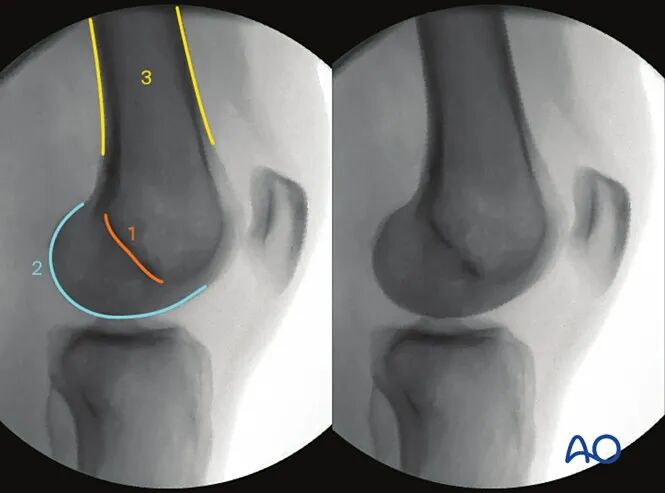

AO干货分享:

看胫骨平台是否平整的透视体位